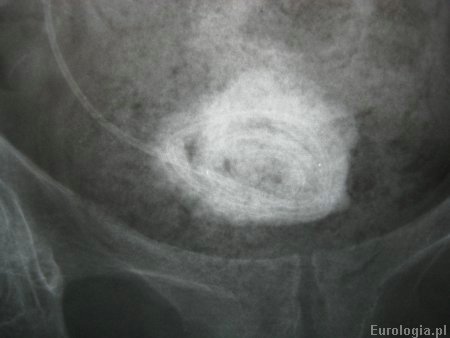

Fot. Kalcyfikacja cewnika DJ - złóg średnicy 5 cm na końcu pęcherzowym cewnika.

Fot. Zdjęcie końca pećherzowego cewnika DJ w powiększeniu.